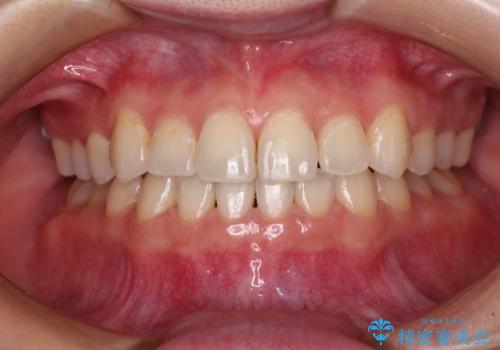

上顎の狭窄歯列 インビザラインによる拡大矯正

- 前歯の叢生と臼歯のクロスバイトを気にして来院された患者様です。

急速拡大装置による上顎の側方拡大を行い、その後はインビザラインより歯列を改善することとしました。

20代後半以降の男性は上顎骨の側方拡大処置の成功率が低く、今回も骨を拡大することができませんでした。

しかしながら、歯列を側方に拡大することができ、その後はインビザラインにて叢生を解消することができました。